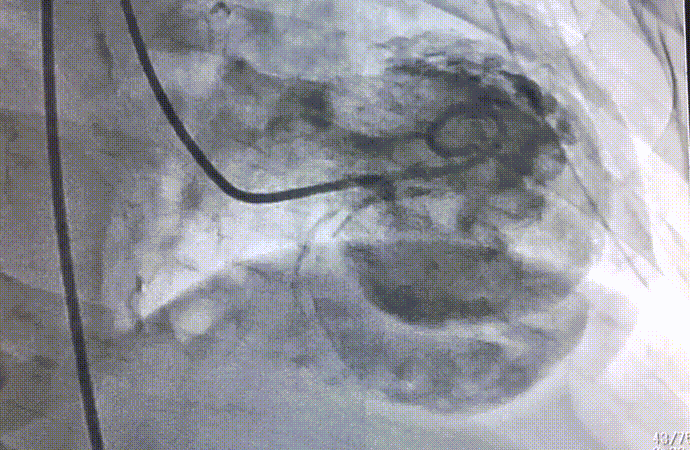

Imagem da Semana

Mais um da série de CATEs temíveis aqui na DozeNews. Paciente com quadro de infarto agudo do miocárdio com supra de ST, complicado com comunicação interventricular (a famosa CIV) - observe o contraste chegando ao ventrículo direito.